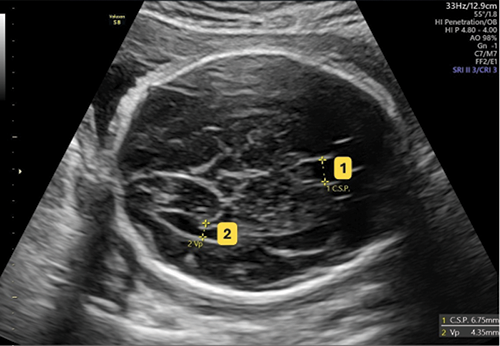

The Value of Early Pregnancy Assessment Clinic in the Improvement of Quality of Antenatal Care

Chanya Pitaksakpong, MD¹, Uravee Limpivest, MD¹, Komsun Suwannarurk, MD¹, Nop Khongthon, MD², Yanwadee Chitkoolsamphan³, Densak Pongrojpaw, MD¹

410